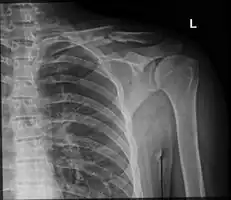

Clavicle fracture

The basic method to check for a clavicle fracture is by an X-ray of the clavicle to determine the fracture type and extent of injury. In former times, X-rays were taken of both clavicle bones for comparison purposes. Due to the curved shape in a tilted plane X-rays are typically oriented with ~15° upwards facing tilt from the front. In more severe cases, a computerized tomography (CT) or magnetic resonance imaging (MRI) scan is taken. However, the standard method of diagnosis through ultrasound imaging performed in the emergency room may be equally accurate in children.[6]